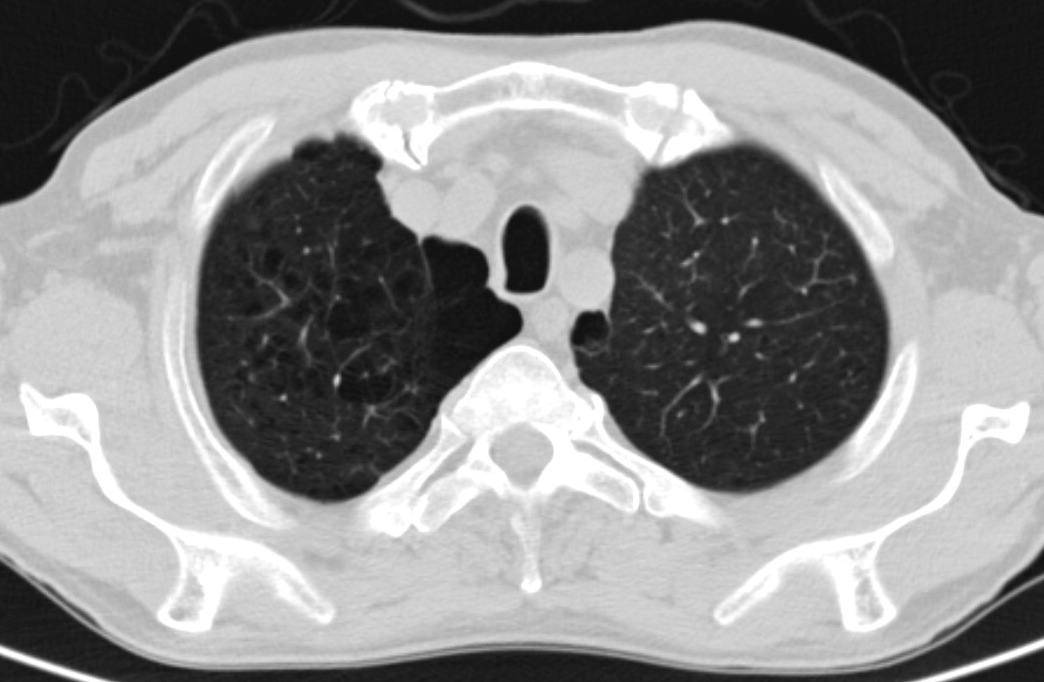

Unklare verdichtungen der lunge links. CAS Article PubMed Google Scholar. Die konventionelle Röntgenaufnahme der Lunge zeigte bipulmonale laterale Verschattungen verdächtig auf das Vorliegen einer atypischen Pneumonie Abb1. Neben der Lungenfunktionsprüfung werden zur Diagnose einer Lungenfibrose bildgebende Verfahren angewandt.

Differenzierung anhand der Wachstumsrate Die Wachstumsrate ist ein wichtiger Faktor für die Evaluation der Malignitätswahrscheinlichkeit bei unklaren pulmonalen Knoten. In Bauchlage wiederholt werden. Diagnostischer Standard ist eine Röntgenuntersuchung des Thorax in Kombination mit einer Computertomographie.

Dieser medizinische Begriff wurde für Sie übersetzt von. Verdacht auf Erkrankungen der Bronchien der Lunge der Pleura der Thoraxwand des Atemantriebs und der Atemmuskulatur. In addition to pneumology and pathology radiology is an essential discipline in the interdisciplinary diagnosis of interstitial lung diseases ILDs.

Verdacht auf Erkrankungen der Bronchien der Lunge der Pleura der Thoraxwand des Atemantriebs und der Atemmuskulatur. Neben der Lungenfunktionsprüfung werden zur Diagnose einer Lungenfibrose bildgebende Verfahren angewandt. Krankheiten die sich in den Alveolen dem terminalen Luftraum der Lunge abspielen haben ein anderes radiologisches Bild als solche die im Interstitium der Lunge lokalisiert sind. Verdichtung Röntgen Lunge. Die betroffenen Bereiche der Lunge sehen dann auf den CT-Bildern heller aus als das gesunde Lungengewebe. Wenn die hellen Stellen in der Lunge die Form eines Streifens haben dann sagt der Arzt dazu streifige Verdichtung. Es wird meist in der Neonatalperiode diagnostiziert und manifestiert sich klinisch in einer unterschiedlich ausgeprägten Tachypnoe. Die optimale Perfusions- und Ventilationsverteilung an dieser komplexen Oberflächenstruktur ist Voraussetzung für deren Diffusionseigenschaften Abb. Schranz Kinderherzzentrum der Universität Gießen danken.